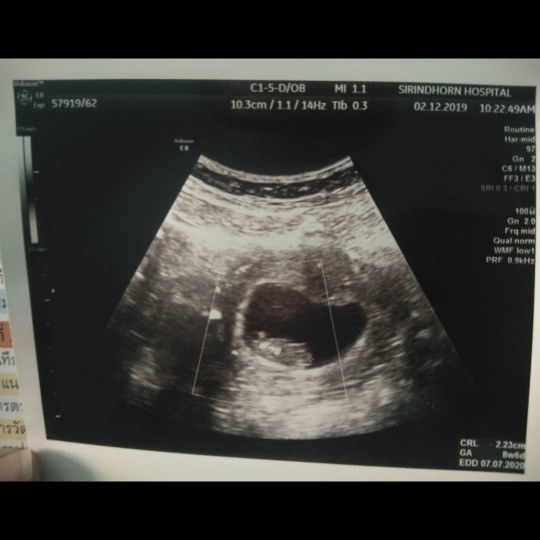

8W+6D ยังไม่เห็นอะไรเลยเหมือนกันค่ะ